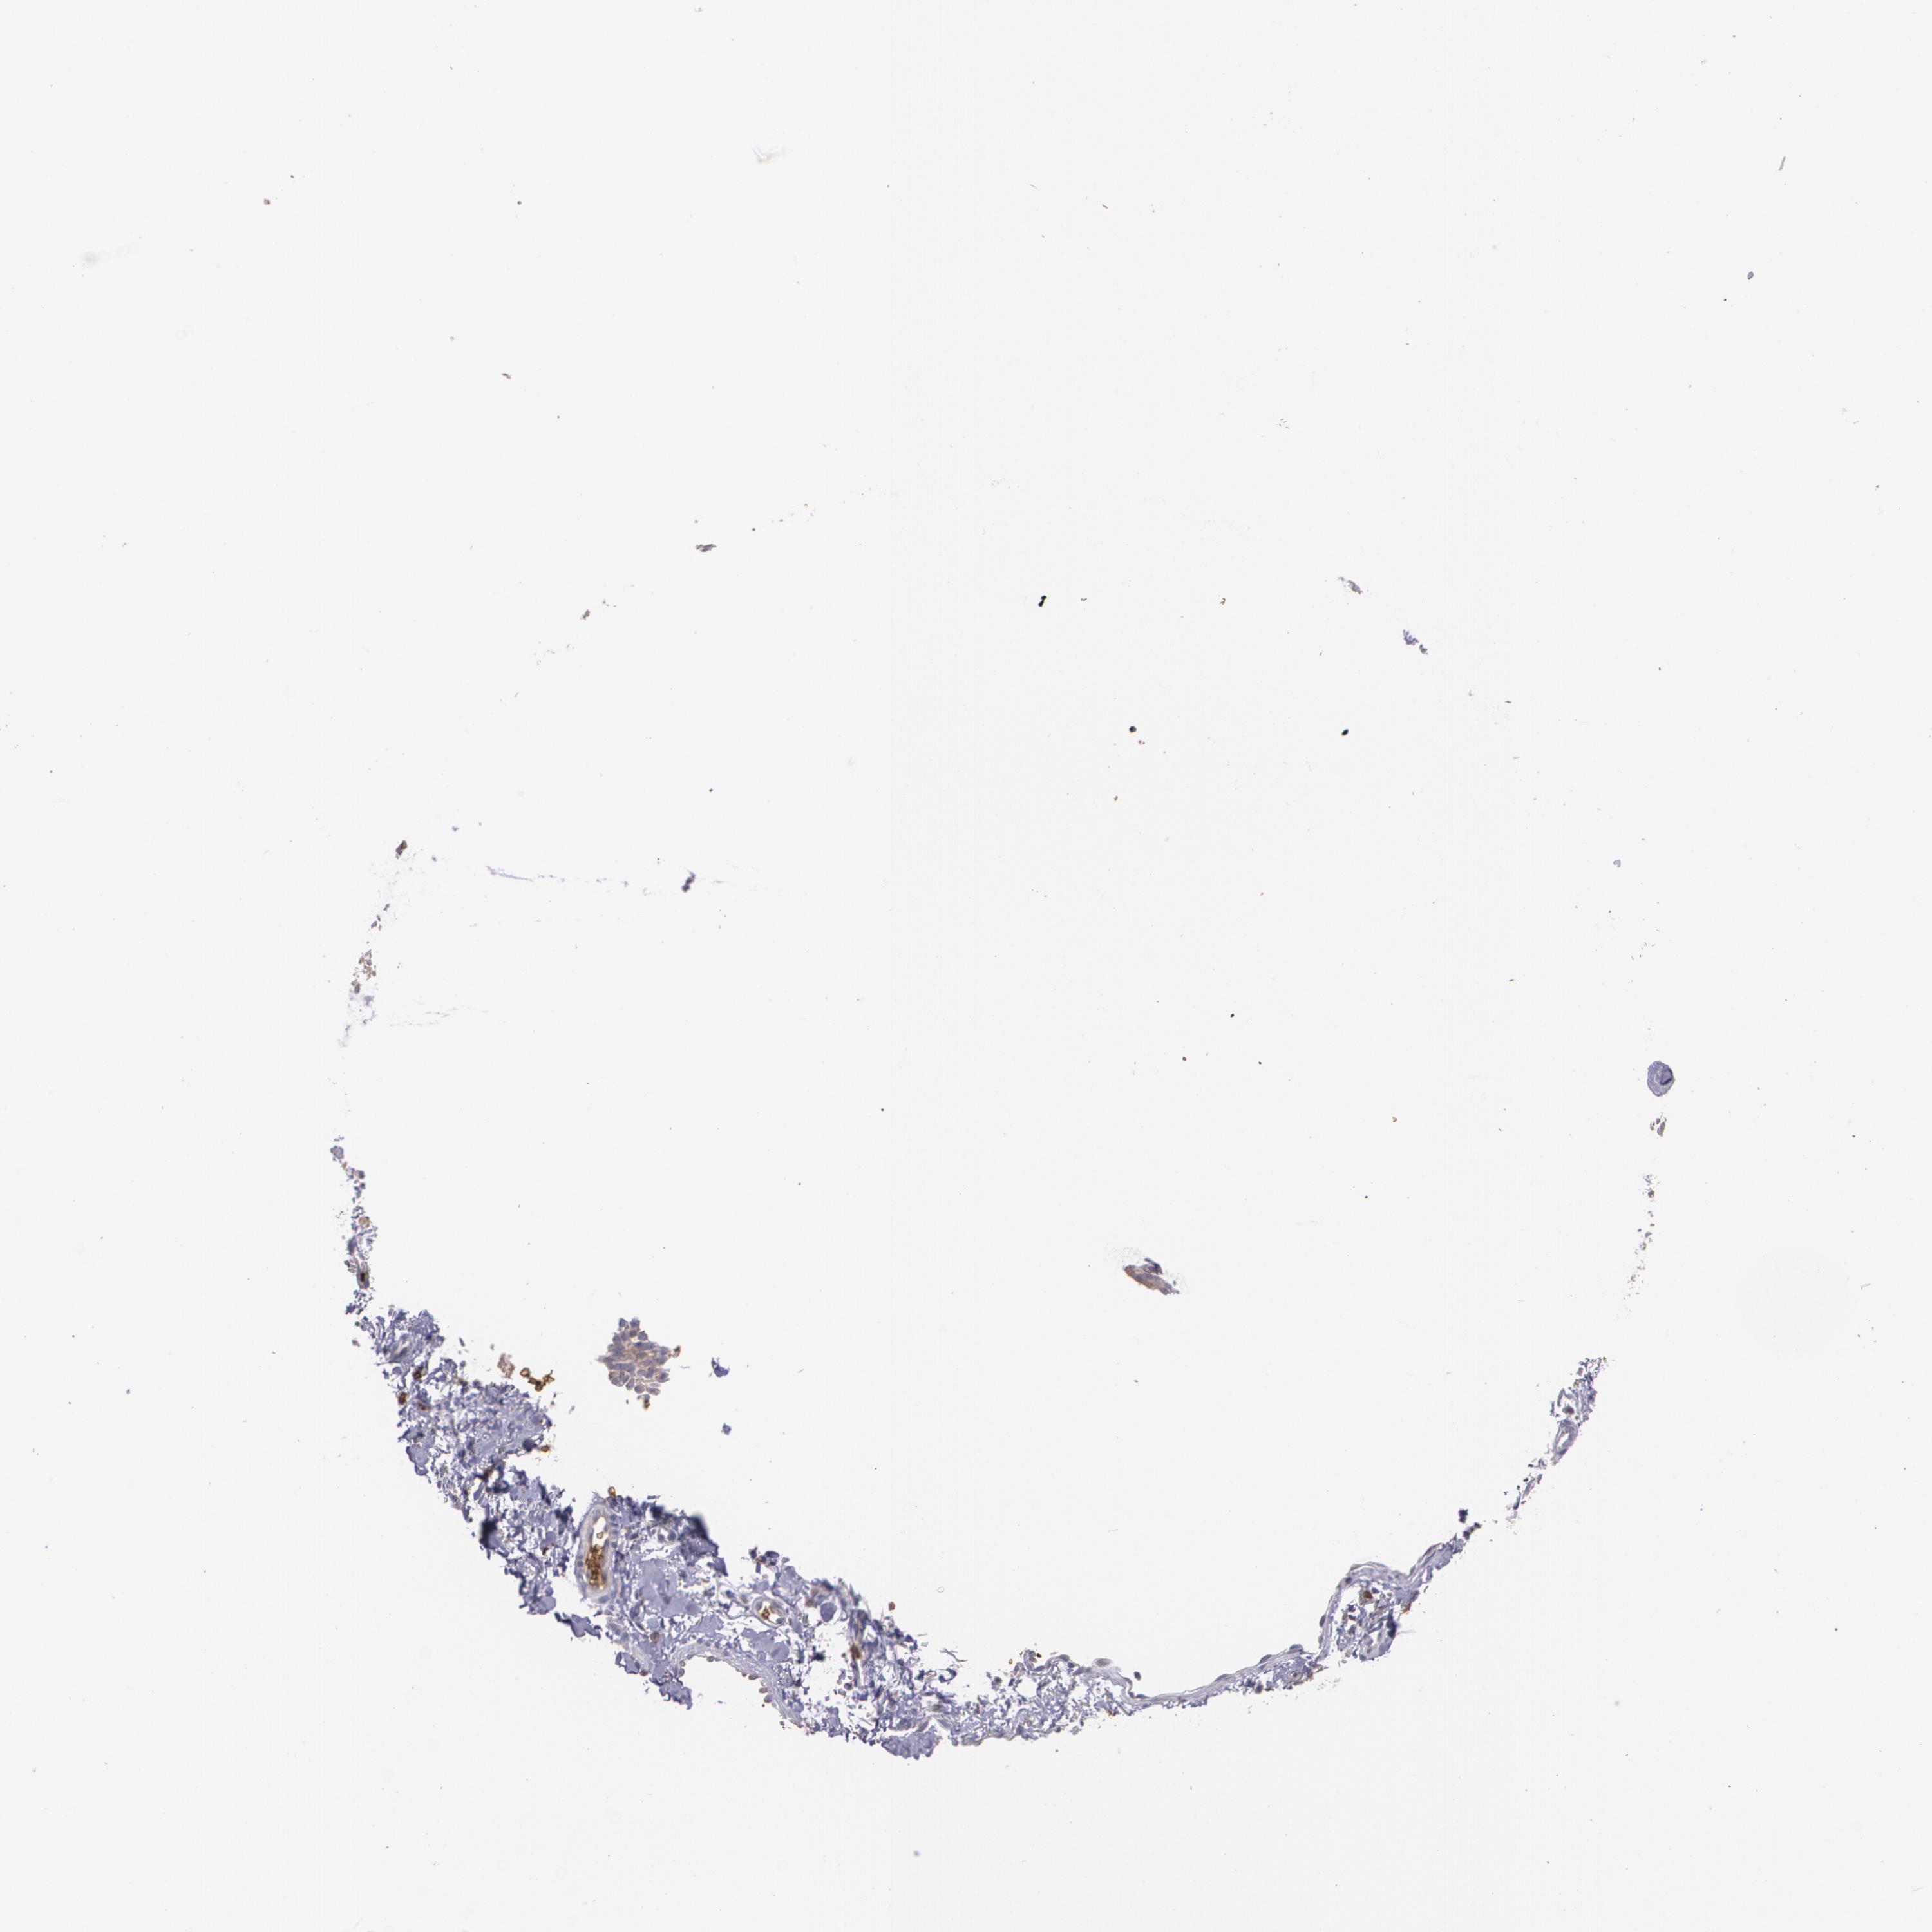

Basal cell and squamous cell cancer

SKIN CANCER - Protein expressioni

A mouse-over function shows sample information and annotation data. Click on an image to view it in a full screen mode. Samples can be filtered based on level of antibody staining by selecting one or several of the following categories: high, medium, low and not detected. The assay and annotation is described here.

Each image is clickable and will lead to virtual microscopy that enables deeper exploration of all samples and also displays staining intensity scores, fraction scores and subcellular localization as well as patient and tissue information for each sample.

Antibody HPA058494

Squamous cell carcinoma, NOS